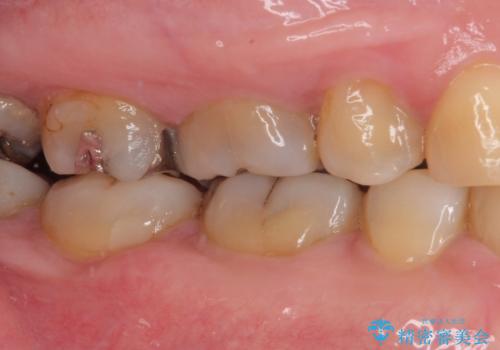

銀歯の下のむし歯 ゴールドクラウンによる補綴治療

- 奥歯で咬んだときに痛みがあり、物が挟まるとのことで来院された患者様です。

咬み合わせが非常に強く、見た目よりも機能と安定性を重視したいとのことで、PGAクラウン(白金加金合金クラウン)にて補綴する治療計画となりました。